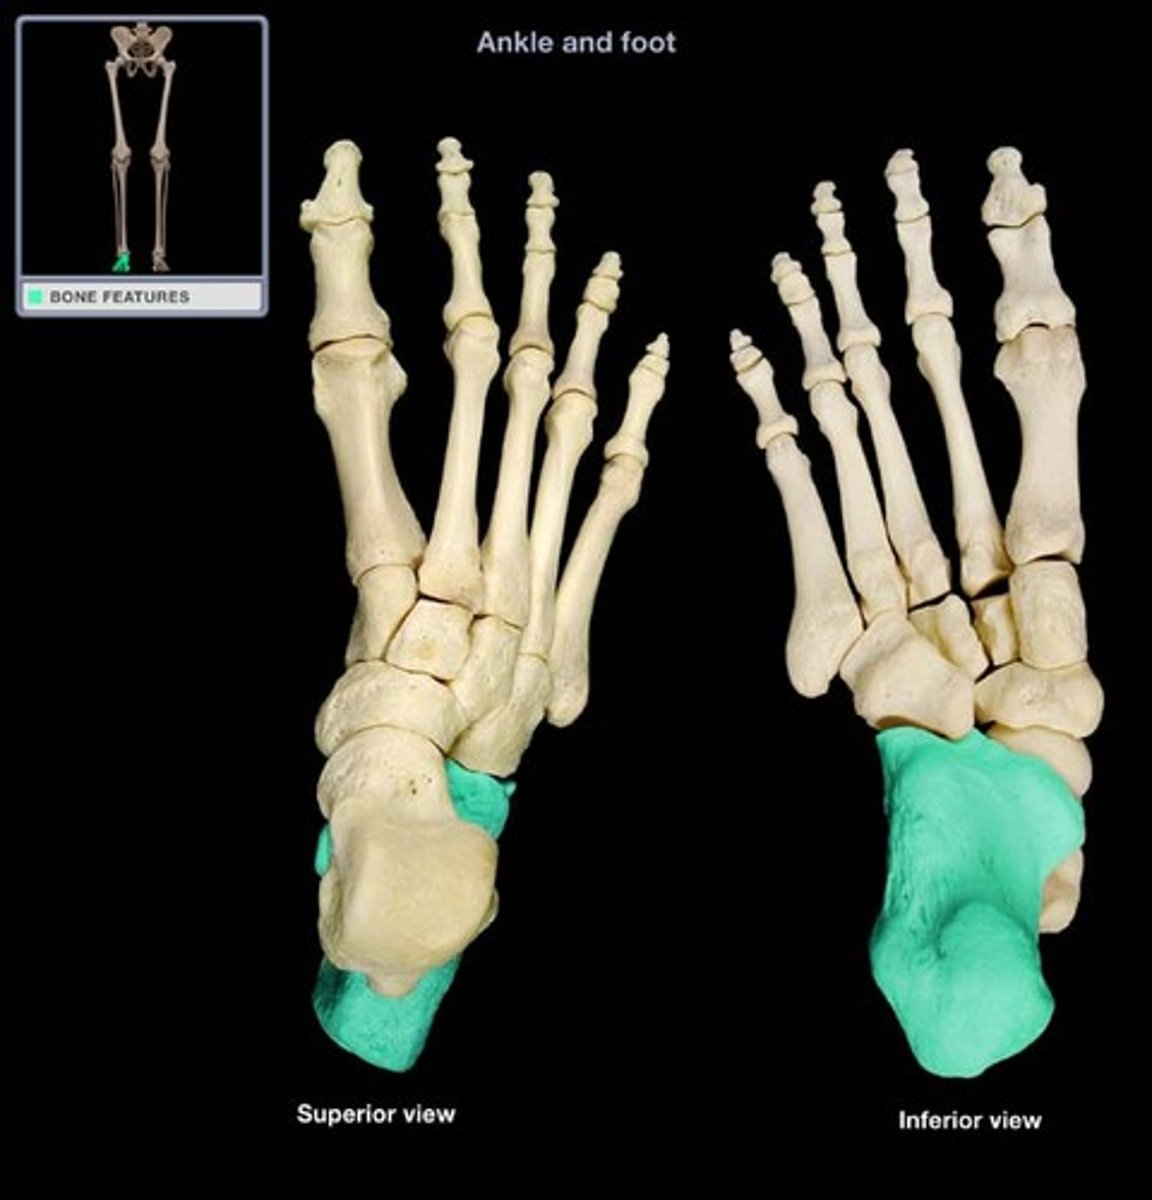

Calcaneus

Calcaneal tuberosity for triceps surae (gastrocnemius and soleus) tendon

Sustentaculum tali (medial shelf for talus)

Posterior talar articular surface

Middle talar articular surface

Anterior talar articular surface

Articular surface for cuboid bone

Navicular

Cuboid bone

Medial cuneiform

Intermediate cuneiform

Lateral cuneiform

First metatarsal

Second metatarsal

Third metatarsal

Fourth metatarsal

Fifth metatarsal